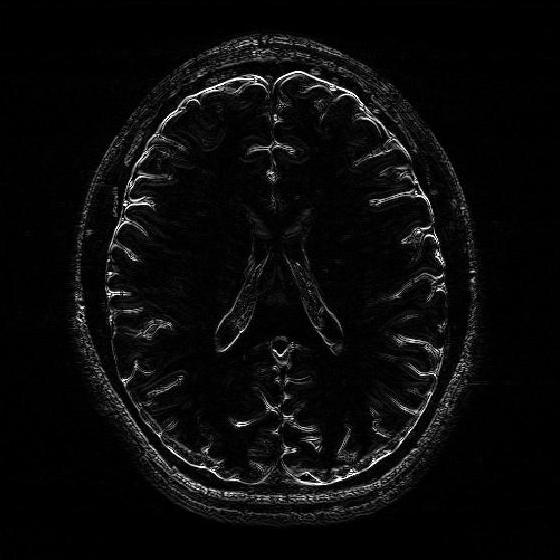

VII-D Application of the 2D-R-FFAST for MR imaging

In this section, we apply the 2D-R-FFAST algorithm to reconstruct a brain image acquired on an MR scanner with dimension . In MR imaging the measurements are acquired in the Fourier domain and the task is to reconstruct the spatial image from significantly less number of Fourier measurements [17]. To reconstruct the full brain image using 2D-R-FFAST, we perform the following two-step procedure:

Differential space signal acquisition: We perform a vertical finite difference operation on the image by multiplying the 2D-DFT signal with . This operation effectively creates an approximately sparse differential image, as shown in Fig. 11(e), in spatial domain and can be reconstructed using 2D-FFAST. Note, that the finite difference operation can be performed on the sub-sampled data and at no point we access all the input Fourier measurements. The differential brain image is then sub-sampled and reconstructed using a stage 2D-FFAST architecture. Also, since the brain image is approximately sparse, we take delay sub-streams in each of the stages of the 2D-FFAST architecture, instead of delay sub-streams as in the exactly sparse case. The 2D-R-FFAST algorithm reconstructs the differential brain image using of Fourier measurements.

-

•

Inversion using fully sampled center frequencies: After reconstructing the differential brain image, as shown in Fig. 11(f), we invert the finite difference operation by dividing the 2D-DFT measurements with . Since the inversion is not stable near the center of the Fourier domain, only the non-center frequencies are inverted. The center region of the 2D-DFT is fully sampled and used in the inversion process.

Overall we use a total of of Fourier measurements to reconstruct the brain image using the 2D-R-FFAST algorithm along with the fully sampled center frequencies. The resulting signal-to-noise ratio of the reconstructed image is dB. While the reconstruction error is not as good as state-of-the-art compressed sensing MRI results, we note that the 2D-R-FFAST has both low computational complexity and low sample complexity , which none of the state-of-the-art compressed sensing results in MRI can achieve.